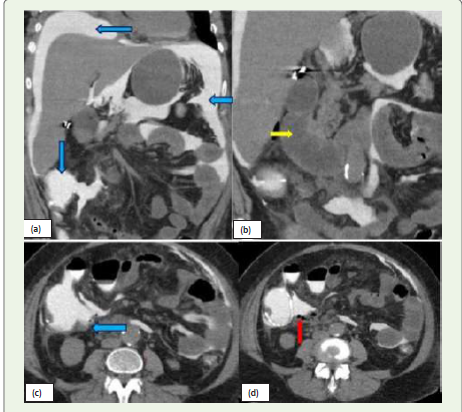

Figure 5: (a, b, c, d):Sagittal, Axial and coronal CT images of a 57-year-old

male patient presents with lower abdominal pain. CT scan of abdomen and

pelvis with oral and IV contrast shows extra-luminal extravasation of oral

contrast adjacent to the ileocecal junction forming a focal collection with air

fluid level in right lower quadrant of the abdomen (blue arrow), suggestive

of anastomotic leak. Additionally, there is formation of another Extraluminal

collection with air-fluid level (purple arrow) is also seen in the pelvis

suggestive of complications.